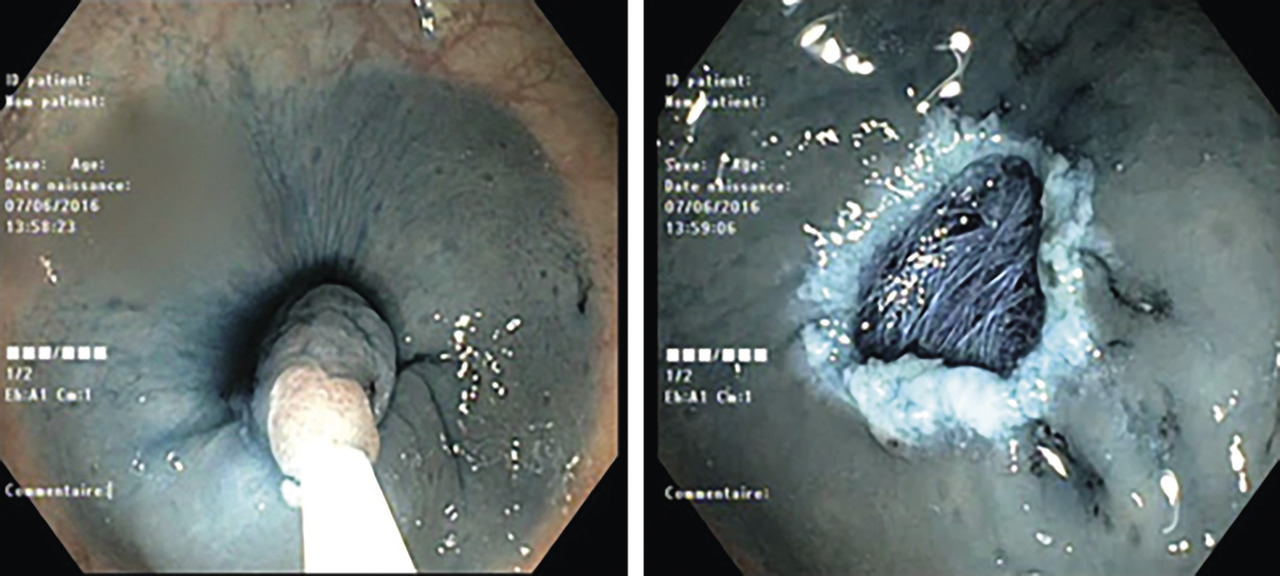

AFS : plus difficiles à dépister, ils sont volontiers plans et ont la même coloration que la muqueuse normale (fig. 1) ; ils sont fréquemment recouverts d’une couche adhérente de mucus qui peut les faire apparaître jaunâtres en lumière blanche, rouges en coloration électronique. Leur différence de structure architecturale se situe dans la partie profonde des cryptes.

Résection à l’anse froide et mucosectomie (fig. 2) : sont à préférer aux autres techniques de destruction ; fournissent une pièce anatomique pour une analyse histologique complète.